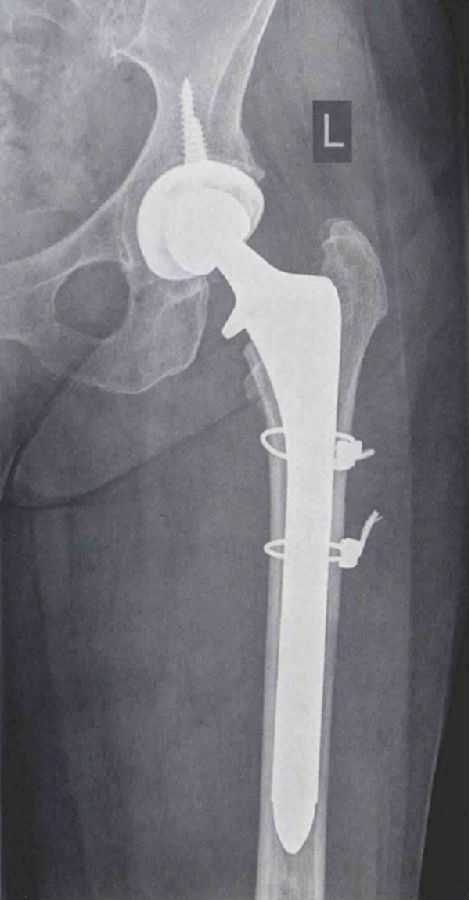

手术使用原切口,并稍向远端延长,以更好地显露近端股骨干。通过后侧入路显露髋关节并脱位,取下股骨头假体,然后仔细分离股外侧肌。在股骨近端发现一处轻微的无移位骨折。取出生物型柄后,使用两股钢丝捆扎复位骨折处。接下来处理股骨,为植入Echelon柄做准备。用铰刀依次从小号扩髓至17号。植入17号Echelon生物型柄后,检查股骨远端固定良好。复位后检查髋关节稳定性良好,下肢长度及偏心距得到充分恢复。

术后,患者可在完全负重下活动。术后X线片显示效果满意(图4和图5)。患者持续恢复良好。3个月随访中,患者完全无不适症状。

图4 左髋翻修术后正位X线片,使用远端固定型柄跨过骨折端,达到良好的远端固定效果1